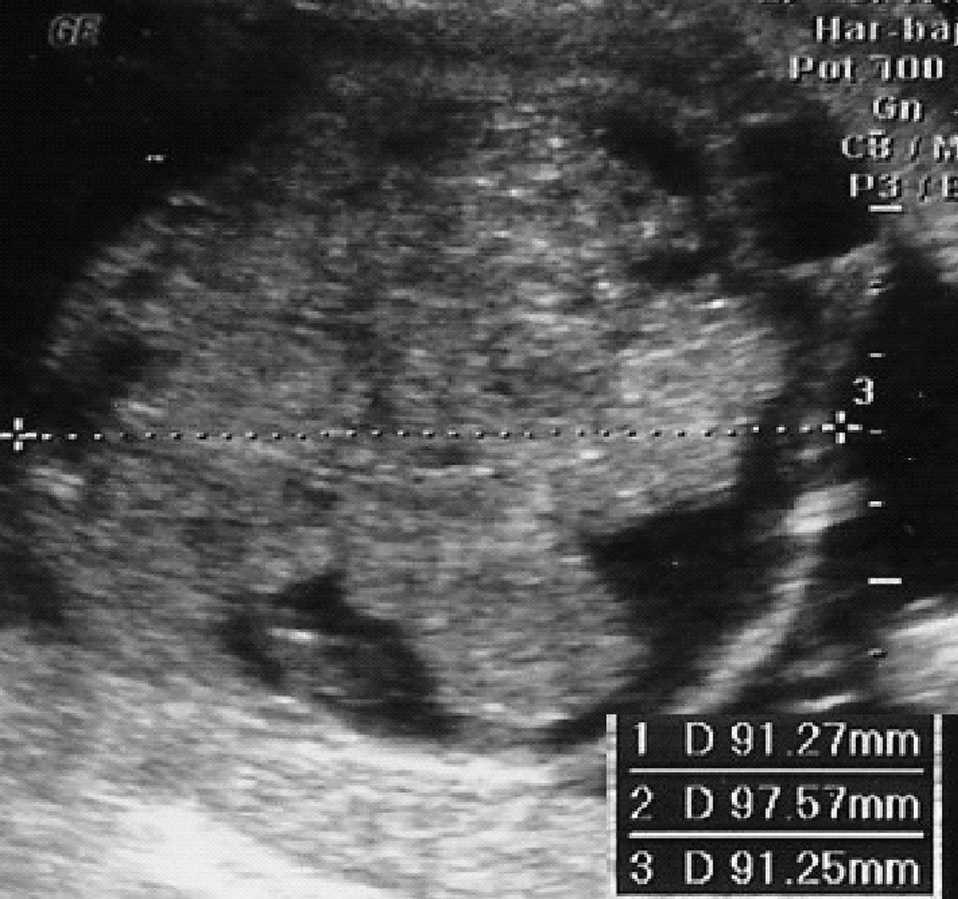

En la siguiente exploración ecográfica, en la semana 25 + 3, se observó un crecimiento de la tumoración con diámetros de 91 × 97 × 91 mm (fig. 3). No se observaban signos de sobrecarga cardíaca, y el Doppler del ductus venoso y la arteria cerebral media eran normales. Como hallazgo adicional a la ecografía anterior, se constató una pielectasia bilateral de 9 mm y un hidramnios (ILA 28) (fig. 4).

Figura 3. Ecografía realizada en la semana 25, donde se observa el crecimiento de la tumoración que mide 91 × 97 × 91 mm.